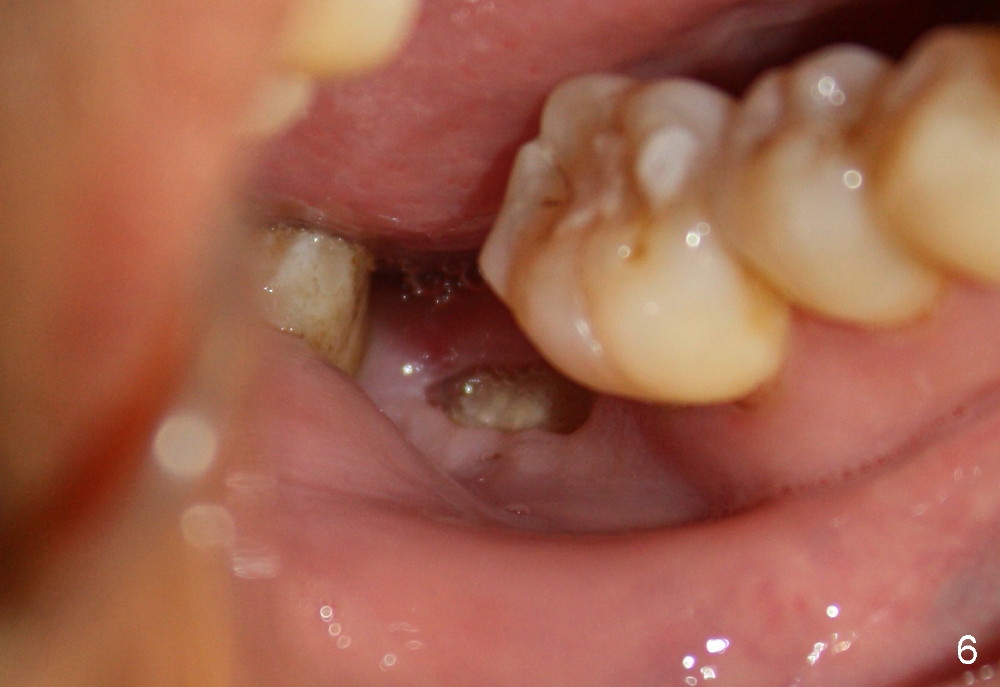

Intraop PA with a radiopaque instrument in the socket reveal the socket is large (Fig.2 arrows). The latter is filled with bone graft (Fig.3 arrows) and collagen plug (Fig.4). Fig.5 and 6 show wound healing 7 and 13 days postop. The ridge is not atrophic 4 months postop (Fig.7), ready for implant.